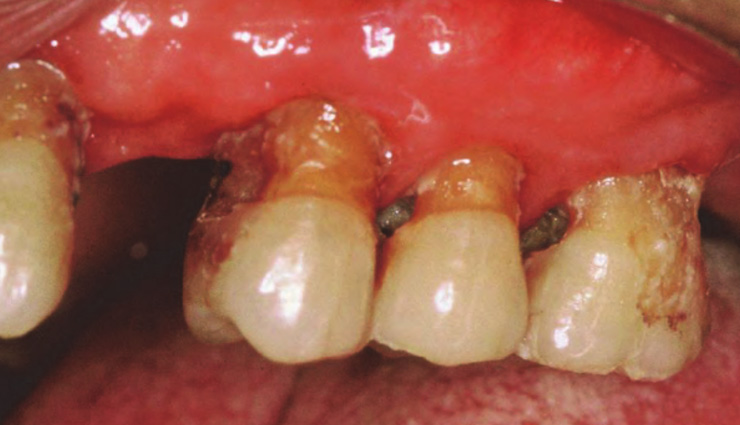

# Gum Diseases

Gum diseases in the elderly are often caused by plaque buildup, food debris, smoking, poorly fitted dentures, an unhealthy diet, and conditions like diabetes. Gum infections can result in loose teeth and bad breath.